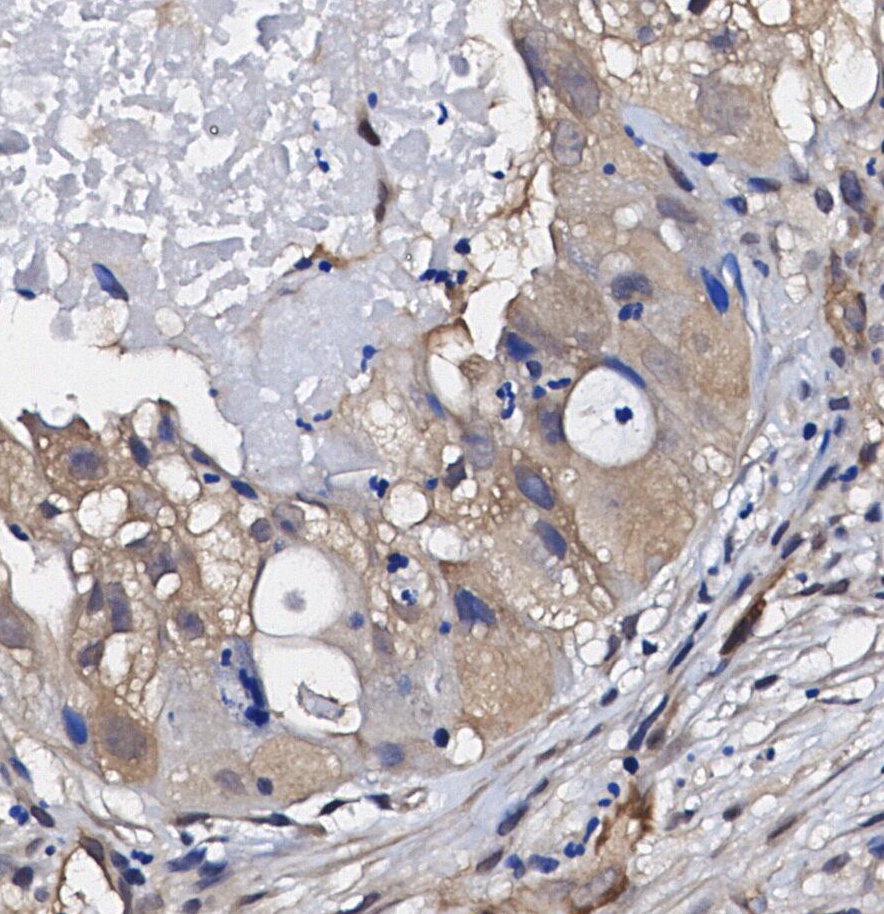

• Immunohistochemical analysis of formalin fixed paraffin embedded human Lung adenocarcinoma tissue with F1285 at 1/100 dilution.